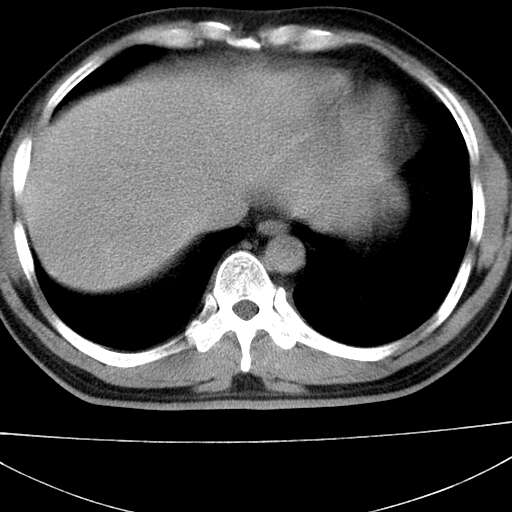

标题: CT21921:腹膜后腔肿物。患者男39Y。体检。增强扫描时间欠准

左侧膈肌脚外缘见一结节样软组织影,密度较均匀,与胸膜关系稍密切,增强轻度强化;考虑来自胸膜良性病变(胸膜纤维瘤可能)。建议加扫胸部ct检查。

2、左下膈肌脚外缘结节状病变,与胸膜交界面呈锐角,胸膜下脂肪线可见,定位于肺内,考虑支气管囊肿或肺隔离征可能性大。

膈疝

左膈肌连续性中断,左侧膈疝可能性大.

左膈肌角后腹膜腔见肿物影,其内见脂肪密度灶及软组织密度灶,强化不明显。病灶大部在后腹膜内。考虑异位嗜铬细胞瘤或脂肪肉瘤、畸胎瘤

左膈肌连续性中断,左侧膈疝可能性大

左下肺隔离症,可见从胸主动脉发出异常血管供应